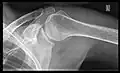

Imaging of the shoulder includes ultrasound, X-ray and MRI, and is guided by the suspected diagnosis and presenting symptoms.

Conventional x-rays and ultrasonography are the primary tools used to confirm a diagnosis of injuries sustained to the rotator cuff. For extended clinical questions, imaging through Magnetic Resonance with or without intraarticular contrast agent is indicated.

Hodler et al. recommend starting scanning with conventional x-rays taken from at least two planes, since this method gives a wide first impression and even has the chance of exposing any frequent shoulder pathologies, i.e., decompensated rotator cuff tears, tendinitis calcarea, dislocations, fractures, usures, and/or osteophytes. Furthermore, x-rays are required for the planning of an optimal CT or MR image.[25]

X-ray

Projectional radiography views of the shoulder include: